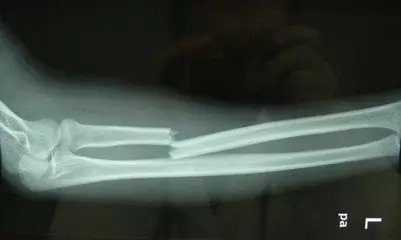

筆者有一遠方親戚,在干活時脛骨被砸,嚴重骨折。當地鄉鎮醫院醫療水平有限,拒絕收治,便只能去縣醫院接受了手術治療,恢復得較理想,但未痊愈。住院一個半月后便回家了,在家中因行走時閃了一下傷處便復發了,傷口處皮膚破損,流出了膿血,疼痛十分嚴重,不能動彈。由于距離醫院較遠,便只能派人去請來當地的一個接骨匠(在農村,會有一些人專門跟隨有經驗的醫生學習接骨,這些人成為接骨匠)。這個接骨匠看了之后,也沒說什么,簡單地處理了一下傷口,用夾板固定了骨折處。然后讓傷者家屬和他一起回家去配藥。

這個接骨匠并沒有把藥方告訴傷者的家屬,只是配好藥后,讓傷者家屬幫忙煎。煎好后,只讓把藥湯帶走了,藥渣卻不讓帶走。筆者的親戚服了 1劑藥,疼痛便有所緩解了 ,一 共服了 5劑,基本上就好了。